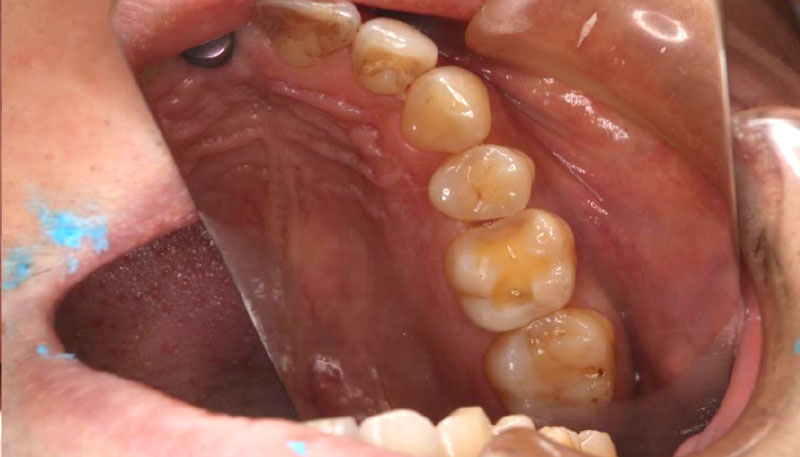

Case.03

インプラントの症例 インプラントの症例

治療前〜治療後のレントゲン写真

患者様の要望過去に治療したブリッジを外し咬み合わせの平面を整えて、被せ物や詰め物を綺麗にしたい。

治療期間10ヶ月

治療費用約1,600,000円

治療内容インプラント2本、アンカースクリューを用いた部分矯正、

セラミックによる補綴治療

治療のリスクセラミックの破折の

可能性